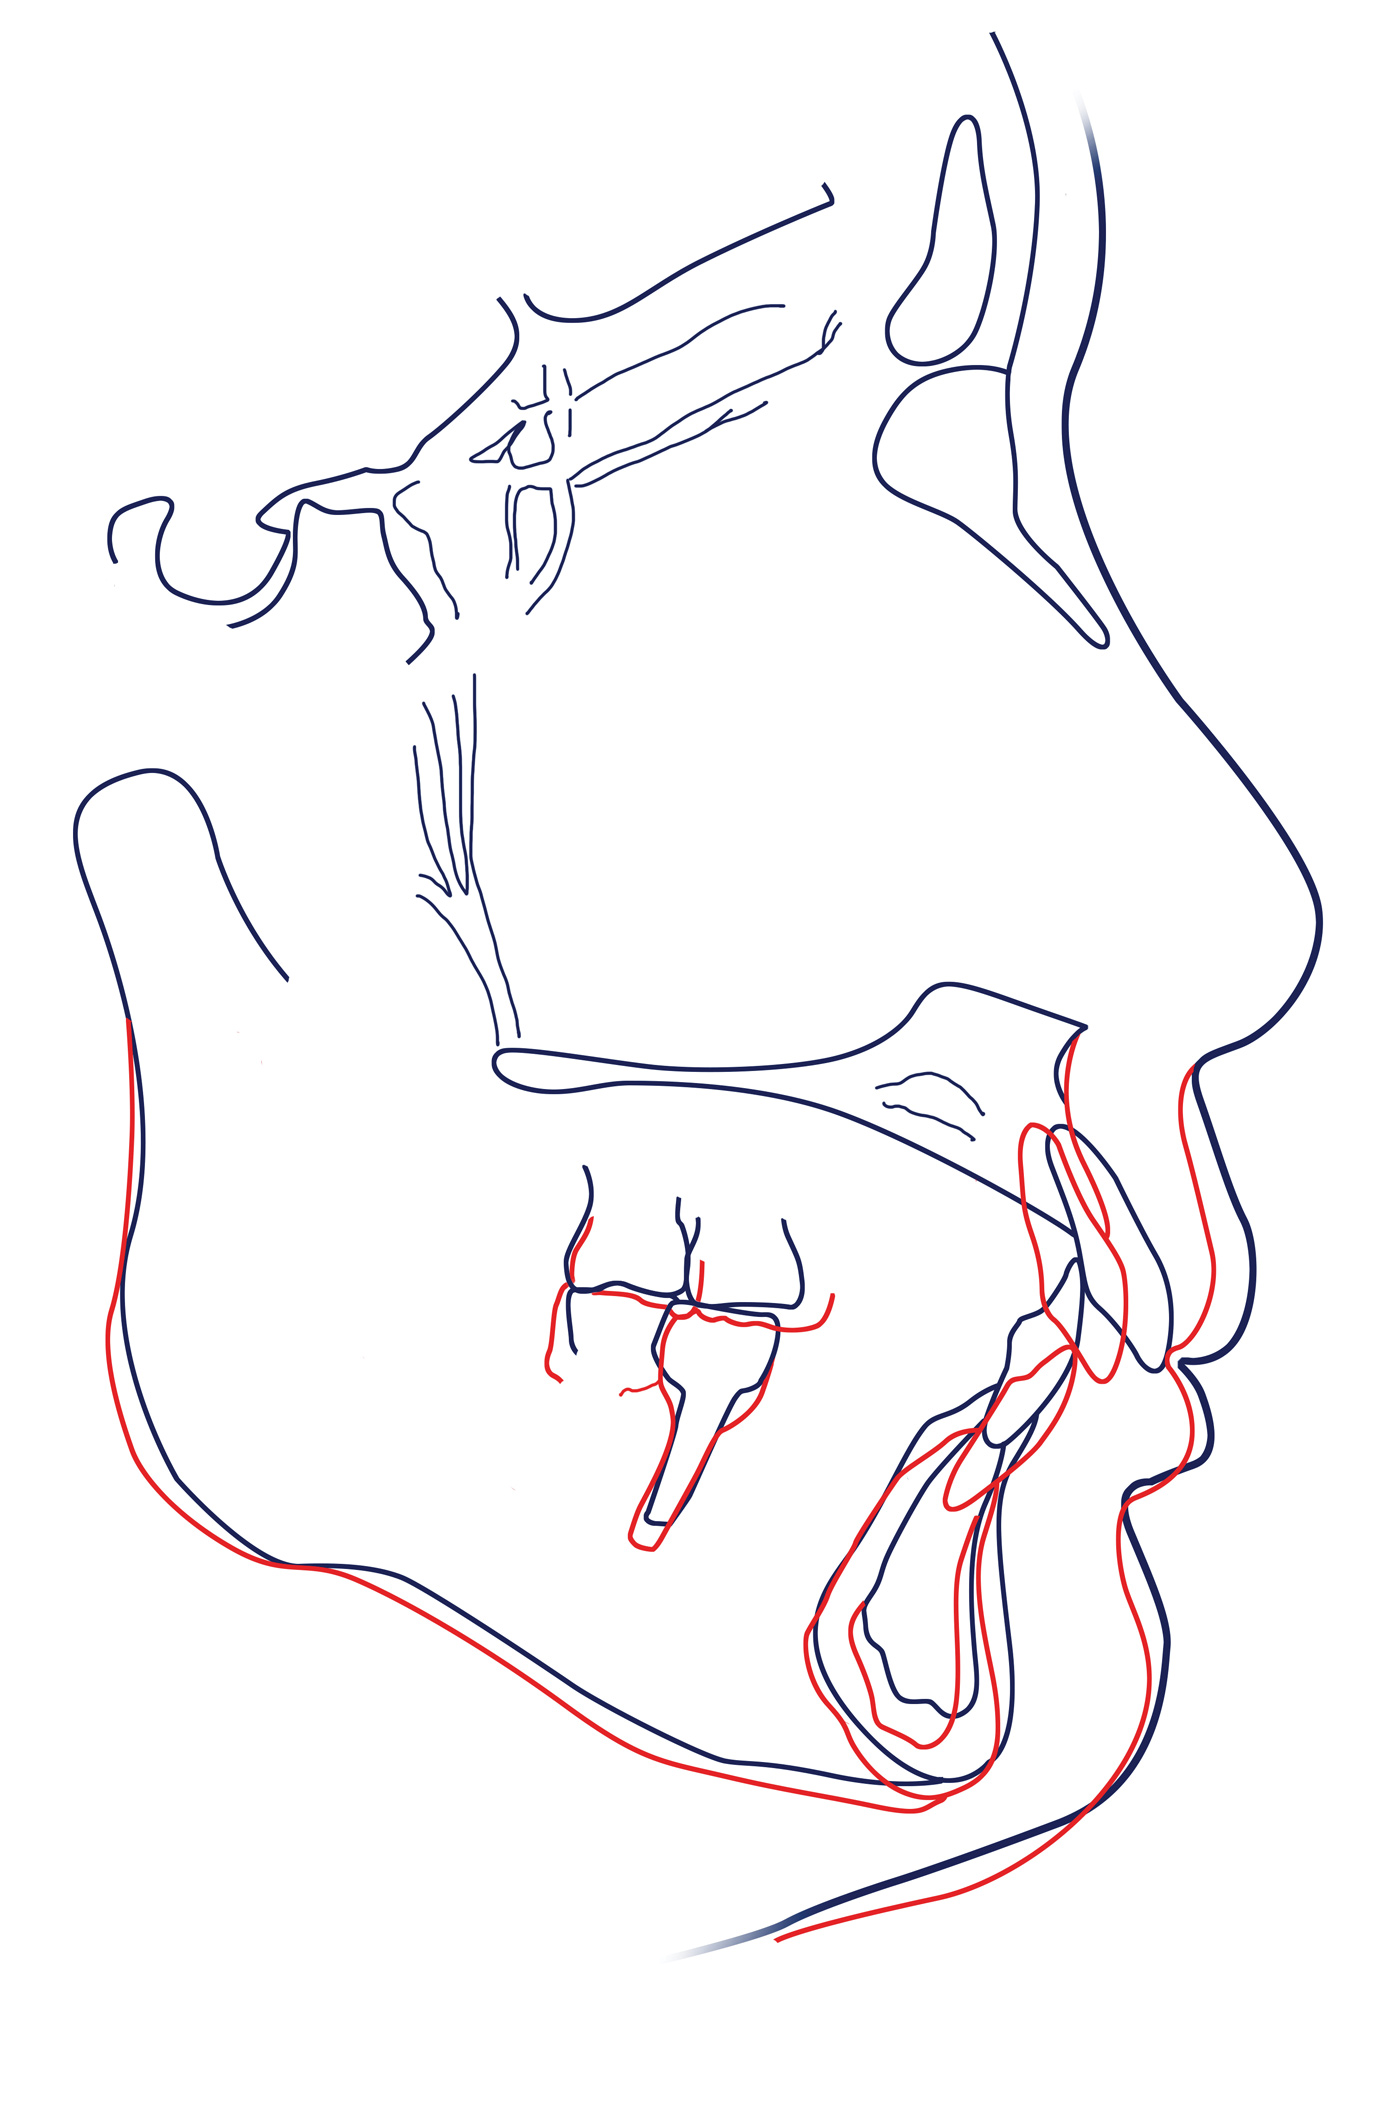

Cephalometric superimposition showed almost complete bodily retraction of the upper anterior teeth and intrusion-proclination of the lower anterior teeth. The upper and lower molars demonstrated extrusion of the coronal portions as a result of prosthetic crown fabrication, resulting in a clockwise rotation of the mandible (Figure 13 and Figure 14). The vertical dimension was successfully increased by 3 mm, and LAFH was improved.

Fig 14. Cephalometric superimposition; black lines indicate pretreatment, and red lines indicate post-treatment.

Figure 14